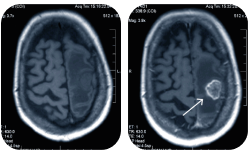

• КТ головы

КТ головы

Компьютерная томография головы в Клинике Эксперт в Мурманске -  это метод медицинского обследования. Его назначают, когда необходимо определить состояние костей и сосудов головного мозга.